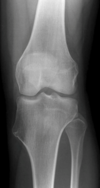

Giant Cell Tumor